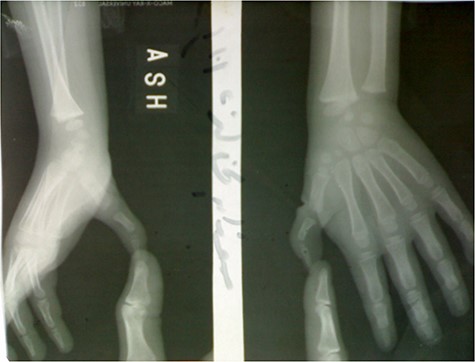

At first examination, the thumb was seen at adduction and flexion position, it cannot be extended, and after passive extension, it returns to original adduction and flexion position (Fig. 1).

There was a contracture and absence at the first web and the thumb was smaller than the opposite left one.

There was no extension in the interphalangeal joint due to the absence of EPL, also in the metacarpophalangeal joint due to the absence of EPB, whereas the CMC joint was stable.